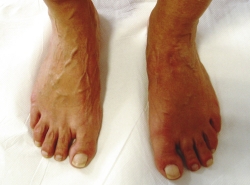

En el estudio mediante radiología simple en carga (Figura 2) se aprecia en la proyección dorsoplantar una desestructuración en la primera cuña con fragmentación y desplazamiento medial del fragmento proximal, así como cambios degenerativos escafocuneanos e intercuneanos. En la proyección lateral vemos un hundimiento de la columna medial a nivel transcuneano. En ambas proyecciones se aprecia una buena consolidación en el pie contralateral (clínicamente asintomático).

Figura 2. Radiografía preoperatoria.